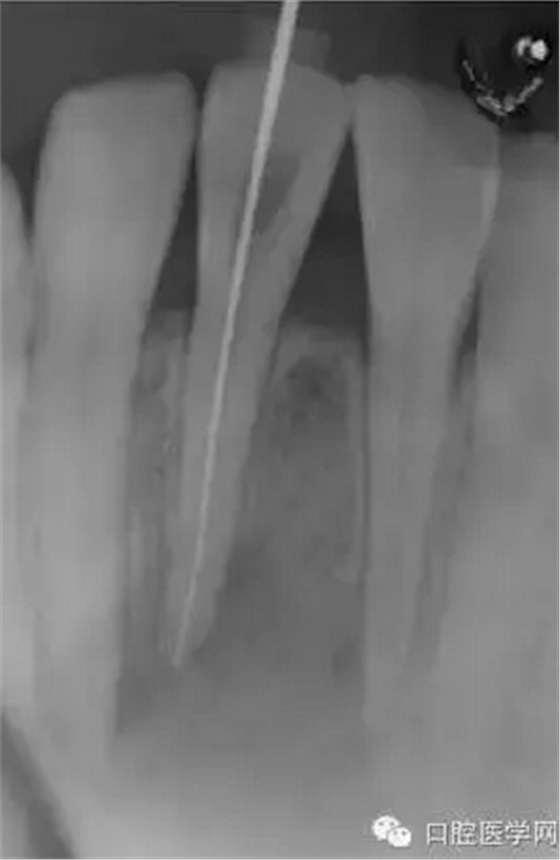

(圖 2) 根管長度測定

就診當(dāng)日進(jìn)行了開髓,測量根管長度及根管成形。開髓時釋放出嚴(yán)重的惡臭,而且可以看到大量膿液通過根管流出來。當(dāng)日于唇側(cè)腫脹部位的最下端進(jìn)行了半月形切口,使膿液從切口處流出,通過根管和切口,使用大量地生理鹽水清洗根尖病灶部位。當(dāng)天根管成形后,為防止食物塞入根管內(nèi),并便于膿液或氣體的排出,使用棉球封住根管口。